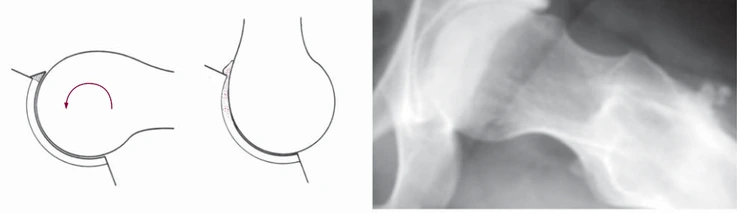

#2. Pincer Impingement

Pincer Impingement는 약간 다릅니다. 대퇴골두의 문제가 아닌, 비구(Acetabulum)의 구조적인 문제로 인해서 대퇴골의 경부와 충돌하면서 발생하는 것입니다. 좌측의 그림을 보면 비구가 본래 정상적인 범주 보다 더 자라나와있는 것을 보게됩니다. 그 부위는 골성조직일수도 있고, 비구순(Labrum)처럼 연부조직일수도 있습니다. 이 부위는 정상적인 고관절(골반)의 움직임에서는 크게 문제가 되지 않지만, 쪼그려 앉기나 높은 곳에 올라가기, 요가동작과 같이 과도한 스트레칭 자세에서 대퇴골 경부(Neck)와 마찰이 되면서 퇴행성 변화를 만들어내게 됩니다. 또한 주로 고관절의 상부에 발생하는 Pincer의 경우 (핀치, 뻰찌) 고관절 굴곡을 제한하고, 더 굴곡하려는 힘에 의해서 대퇴골두를 아랫방향으로 밀어내게 됩니다.(좌측 그림의 우른쪽 빨간색 선부위). 이 문제의 경우 주로 중년의 여성에서 유병율이 높습니다.